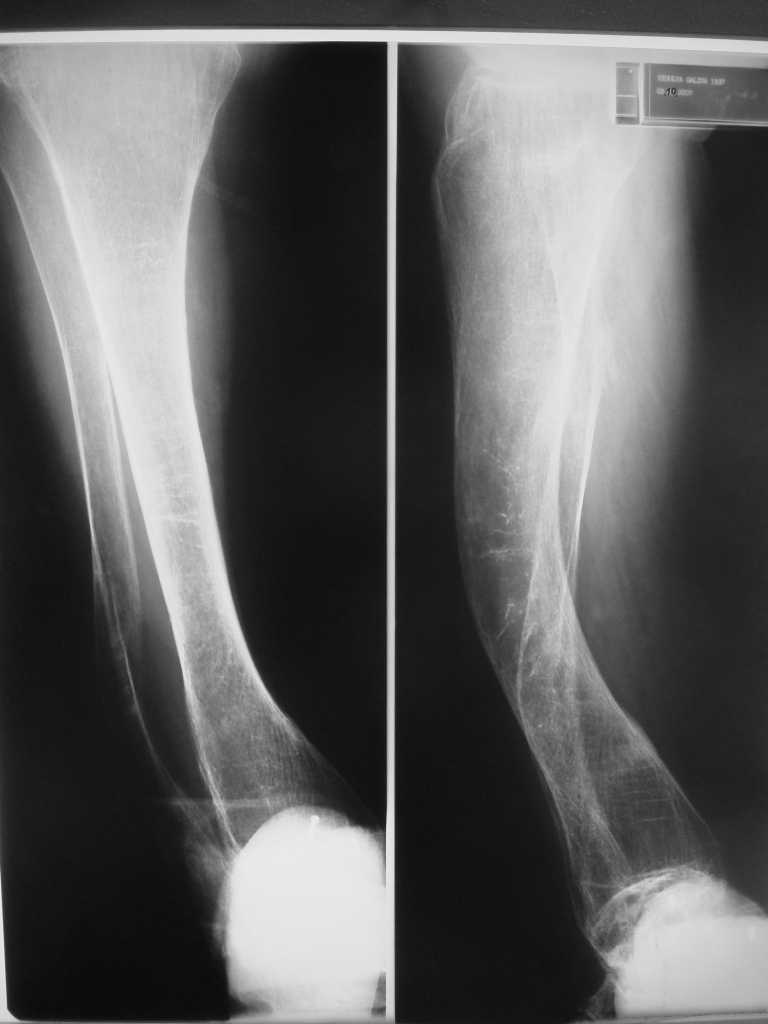

Но даже при малоинвазивной методике лечения применимой для даной больной существуют следующие проблемы: выраженный остеопороз, тонкий кортикал, очень широкий канал.

Контрольные рентгенограммы прилагаю.

Проблема в том, что в сагитальной плоскости угол голеней =30 градусам. Ширина канала 30.

ДС> Проблема в том, что в сагитальной плоскости угол голеней =30 градусам. Ширина канала 30.

Если при введении стержня будет видно, что из-за искривления дело идет к перфорации стенки, надо будет сделать чрескожную остеотомию на уровне кончика стержня.

ДС> Будет ли остеосинтез стержнем стабильный?

Во-1-х, интрамедулярный остеосинтез относится к методам, дающим относительную, не абсолютную стабильность. Во-2-х, стабильность неплохо обеспечивается запирающими винтами. В-3-х, несоответствие кривизны стержня и канала приводит к повышению стабильности, в-4-х, канал можно искусственно сузить введением отклоняющих (трансмедуллярных, Poller) винтов.